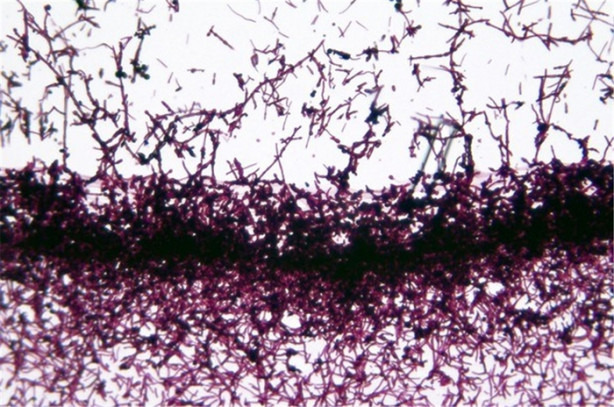

Bir bardak suya sabah aç karnına tükürün ve 15 dakika izleyin.

Eğer tükürük suyun üstünde kalıyorsa sağlıklı bağırsak florasına sahipsiniz. Evdeki herkes testi yapsın.